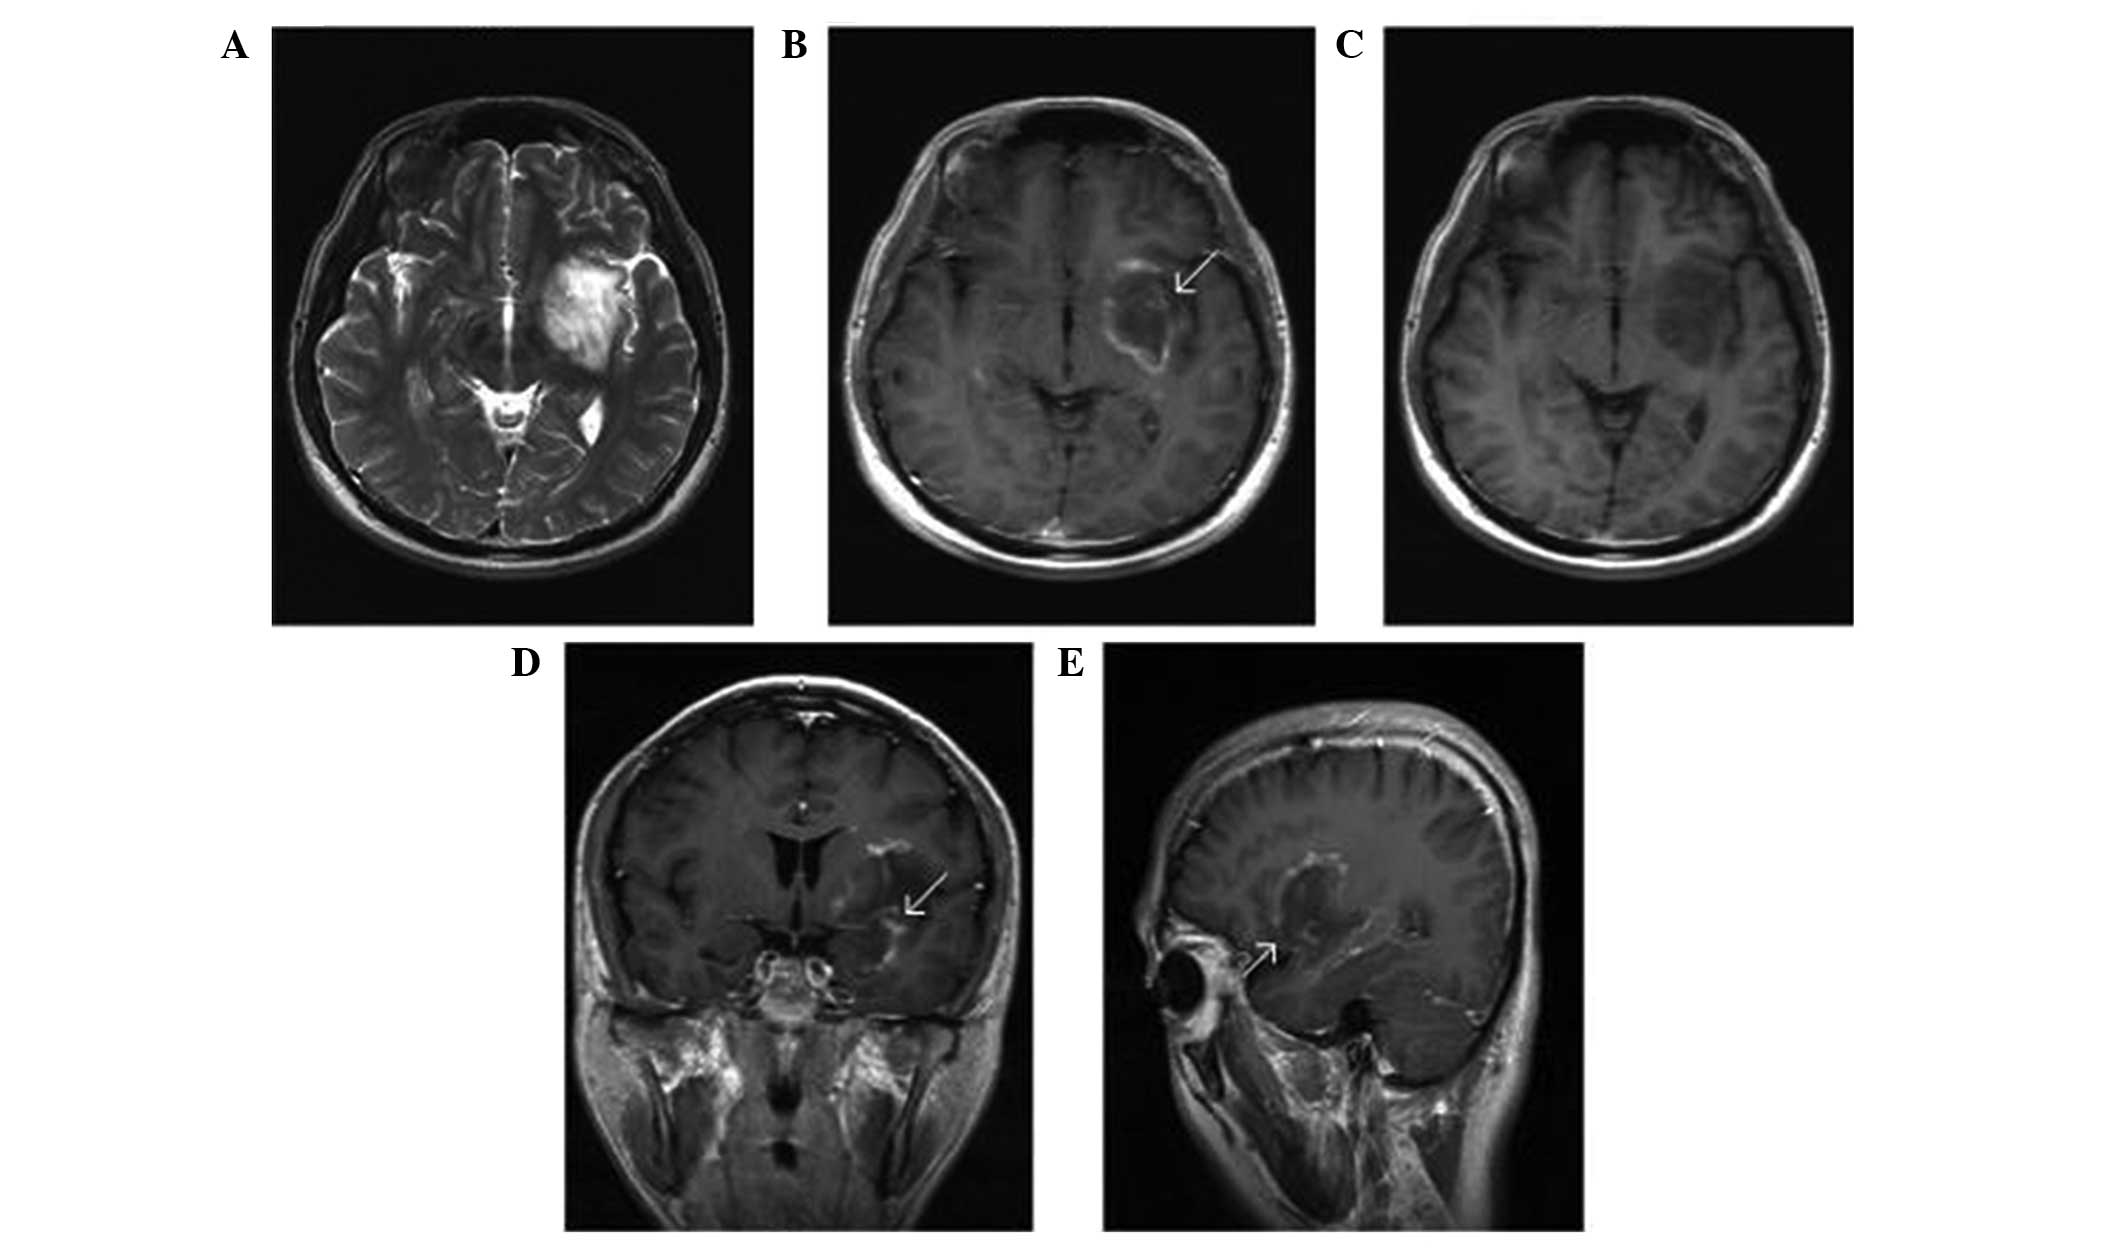

The radiographic features observed in the 14 TDL cases are listed in Table II. The locations of solitary lesions (12 cases) included the following: Frontal lobe (3 cases), temporal lobe (4 cases), parietal lobe (3 cases), insular lobe (1 case) and basilar ganglia area (1 case). Regarding the 2 cases with multiple lesions, in 1 case the lesions were located at the frontal lobe and parietal lobe, while in the other case the lesions were located in the frontal lobe and the pons. The size of the lesions ranged between 2 and 5 cm. On the CT scans, the TDLs were hypodense (9 cases) or heterogeneously dense (5 cases) masses with a well-defined margin and little surrounding edema. On the MRI scans, 12 cases demonstrated local subcortical masses which were hypo-intense on T1-weighted images and hyper-intense on T2-weighted images and fluid-attenuated inversion recovery images, with the exception of 2 cases with heterogeneous signal intensity. A total of 6 cases had a relatively sharp margin and 8 cases had a poorly defined margin, with light to moderate surrounding edema. Following Gd-DTPA administration, all the cases presented variable enhancement, including 5 cases (35.7%) of patchy, 6 cases of open ring-like (42.9%) and 3 cases of ring-like (21.4%) enhancement. In addition, 6 cases demonstrated enhancing vein coursing undistorted through the lesion (Fig. 1).

Figure 1.

Magnetic resonance imaging scans of tumefactive demyelinating lesion. (A) Non-enhanced axial T2-weighted image demonstrating a lesion located within left basal ganglion area. (B) Enhanced axial T1-weighted image revealing ring-like enhancement. (C) Non-enhanced axial T1-weighted image. of the lesion (D) Enhanced coronal T1-weighted image of the lesion. (E) Enhanced coronal T1-weighted image of the lesion. The arrows indicate the area of the lesion.